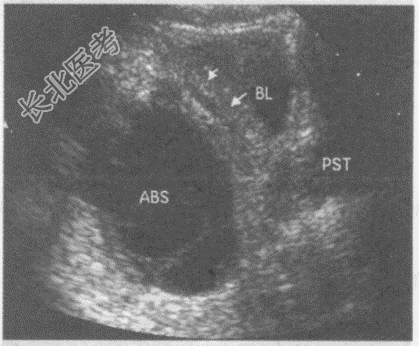

- 单项选择题临床资料:男性患者, 29岁,自诉发热、腹痛、腹坠胀不适十余天。

化验检查: 血常规白细胞、中性粒细胞均增高。

超声综合描述:盆腔可见6.4cm×4.3cm无回声区, 形态不规则,边界欠清晰, 壁不均匀增厚,内透声不清亮, 可见完整及不完整分隔,其旁膀胱壁增厚(箭头所指)。

超声提示:  A、盆腔包裹性积液

B、盆腔脓肿膀胱壁受累增厚

C、肠梗阻肠腔积液

D、淋巴囊肿

E、急性肠炎